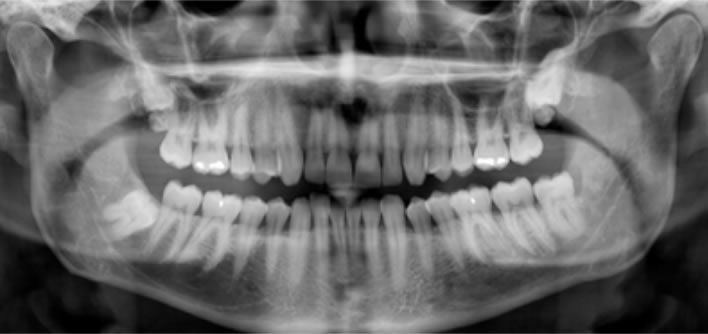

Rengenska snimka cijele čeljusti (Ortopan) koristimo je uvijek prilikom prvog pregleda da bi se vidjelo stanje svih zuba i okolne kosti te tokom kontrolnih snimki kod protetskih i implantoloških radova.

Uređaj koji koristimo prilikom slikanja ortopana snima 5 slojeva snimke unutar jedne ekspozicije tako da se dobije što bolji prikaz čeljusti i zubi.